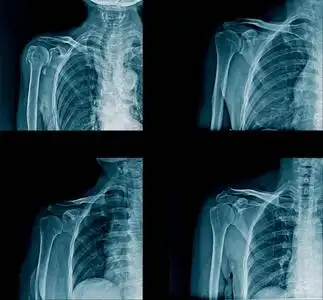

肩关节x线检查体位大全

肩关节正位-x线图

肩部肌肉肩部肌肉蓝色肩部x线图像及横幅设计,黑色背景锁骨骨折固定